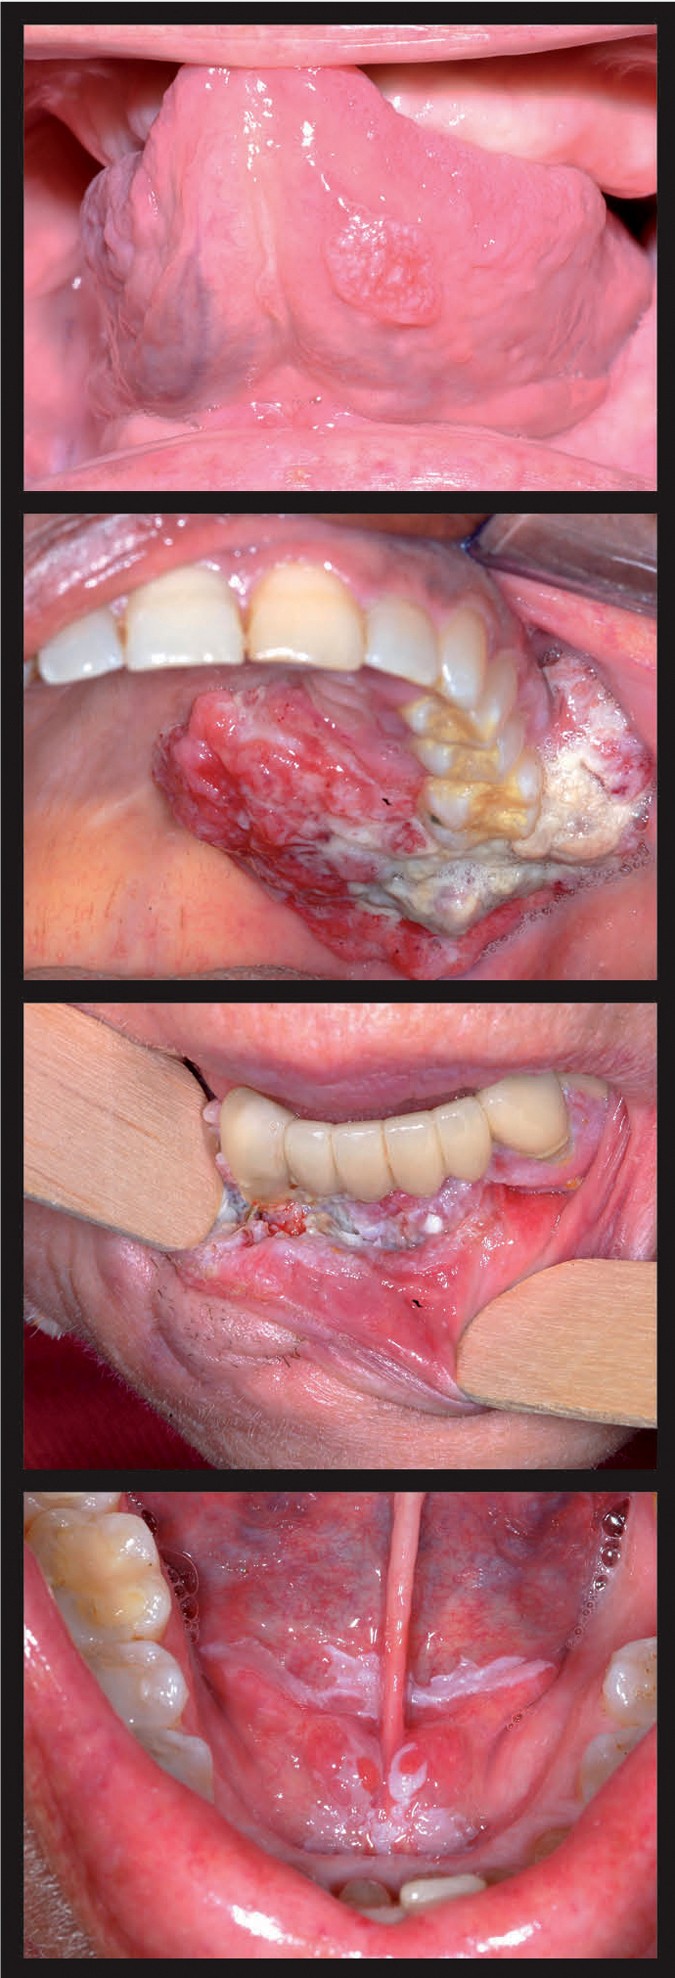

What Does Mouth Cancer Look Like 5 Pictures Of Mouth Cancer

Visual Guide To Oral Cancer

Oral Cancer Images The Oral Cancer Foundation

Lesion On The Anterior Floor Of The Mouth With Irregular

Clinical Assessment Of A Squamous Cell Carcinoma Located In

Oral Cancer Images The Oral Cancer Foundation